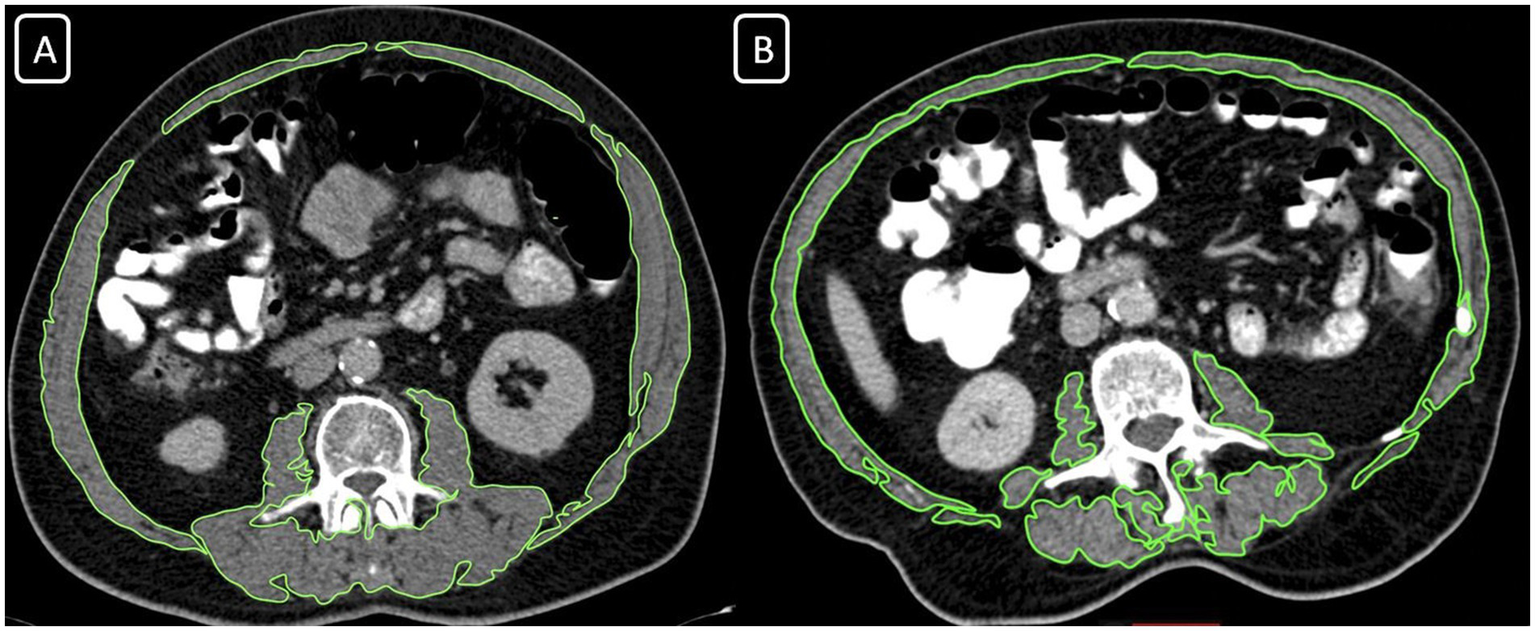

The assessment of skeletal muscle mass (SMM) was performed by contrast-enhanced thoracoabdominal computed tomography (CT) for each patient as a routine evaluation for oncological staging (Siemens Somatom Sensation 64 Detector). For determining the SMM measurements; an axial portal-phase image was obtained at the level of the third lumbar (L3) vertebra. Two radiologists evaluated the images, one with over 15 years of academic experience and the other with 10 years of experience. The images were evaluated with commercial software (Osirix Lite). The software automatically scanned the images and, according to the specific densities of the different tissues, determined the areas with a density of −29 to 150 Hounsfield Units (HU) as muscle tissues (Figure 1). The radiologists checked, revised, and approved all muscle areas that the software program calculated. Then all muscle areas were measured as cm2. Skeletal muscle mass index (SMMI) was calculated by dividing the muscle area (cm2) by the square of the patient’s height (m2). We used the classification of Martin et al. to determine the groups for SMMI (17). Low SMMI was defined in women with SMI <41 cm2/m2 and men with SMMI <43 cm2/m2 in patients with body mass index (BMI) < 25 kg/m2. Low SMMI was defined in patients with >25 kg/m2 BMI level when their SMMI was lower than 53 cm2/m2 (17). The participants were classified into two groups; patients with Low SMMI, and Normal SMMI results.

Figure 1

Computed tomography images at the L3 vertebral body, revealing the skeletal muscle area (SMA) measurement in two different individuals. (A) SMA = 150.33 cm2 with BMI: 24,7, normal skeletal muscle mass index group; (B) SMA = 150.33 cm2 with BMI: 22,4, low skeletal muscle mass index group.